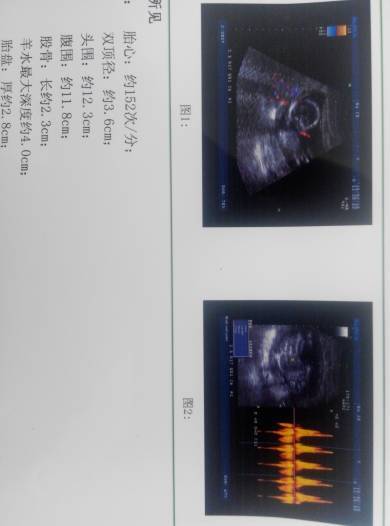

亲们帮我看看这是男是女啊,男女都好,我只是想提前准备宝宝衣服 亲们帮我看看这是男是女啊,男女都好,我只是想提前准备宝宝衣服, 点击展开 雨的偶然 2015-02-15 14:52 为您推荐: 其他回答 您这数据是不能辨别男孩还是女孩的,建议您找熟人检查b超看看,比较准确,也可以做羊水穿刺来确定, laojianghu309 2015-02-15 14:56 相关问题 求大神解答,我这孩子是男是女,我不男女,我给我孩子准备衣服,谢谢啦 6个月肚肚照,会通过肚肚形状看男女的进来,帮我看看是男是女 帮我看看宝宝正常吗?可以看出男女不?